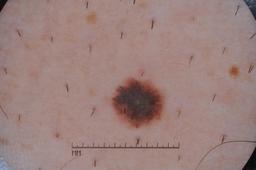

MSK-4

- Name: MSK-4

Description:

Images found based on a search for patients with a personal history, clinical diagnosis, or differential diagnosis of melanoma. All diagnoses confirmed by histopathology.